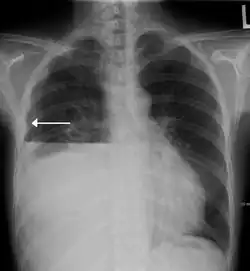

A hydropneumothorax with a white arrow pointing to the lung's pleura

Hydropneumothorax is defined as the presence of both air and fluid within the pleural space.[1] An upright chest x-ray will show air fluid levels. The horizontal fluid level is usually well defined and extends across the whole length of one of the hemithorax.